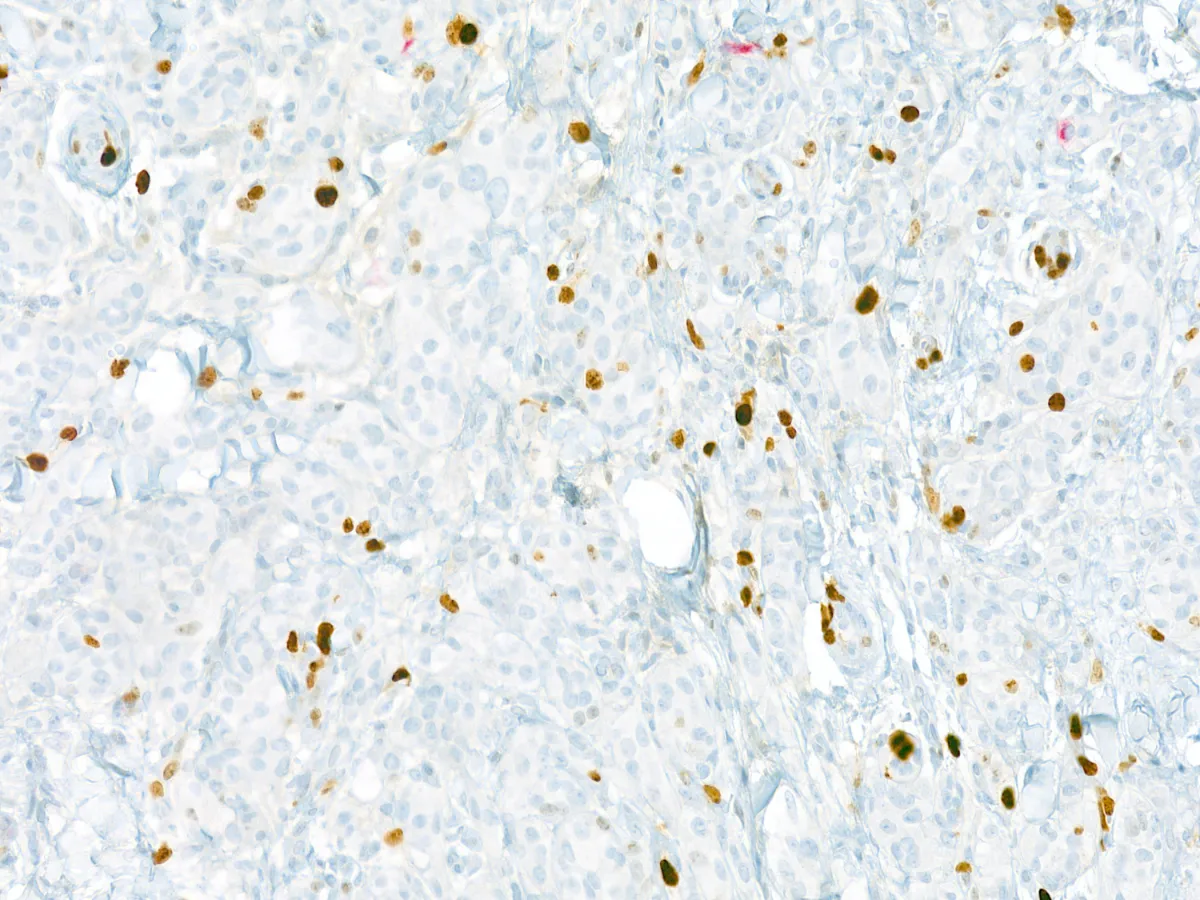

8. MITF 20x

9. SOX10 20x

10. S100 20x

- Todos los tumores expresan SOX10. En un 50% de los casos expresan S100 con patrón difuso. Melan-A/MART-1 y HMB-45 se expresan focalmente. La inmunohistoquímica para TRIM11 es típicamente positiva nuclear en la periferia del tumor. Pueden expresan Pan-TRK (57% citoplasmático difuso, 36% citoplasmático parcheado), a pesar de no tener mutaciones de TRK. PMID: 35993578; PMID: 29240581.